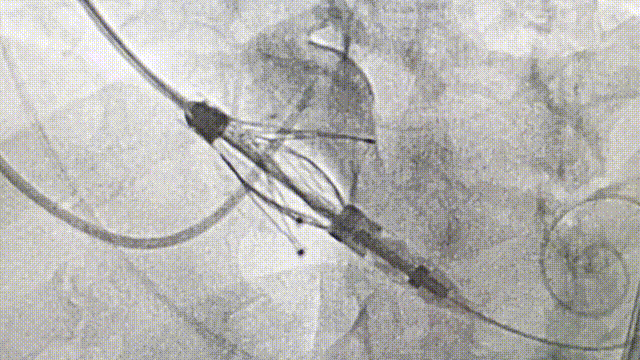

释放后造影(横位心)

释放后造影

整个手术过程非常顺利,两例患者平均用时1.5小时。其中从sheath-in到sheath-out平均时长不到30分钟。重度主动脉瓣反流即刻消失,无瓣周漏,患者血流动力学迅速改善;超声及DSA多模态影像进一步证实瓣膜释放位置优异,功能良好。